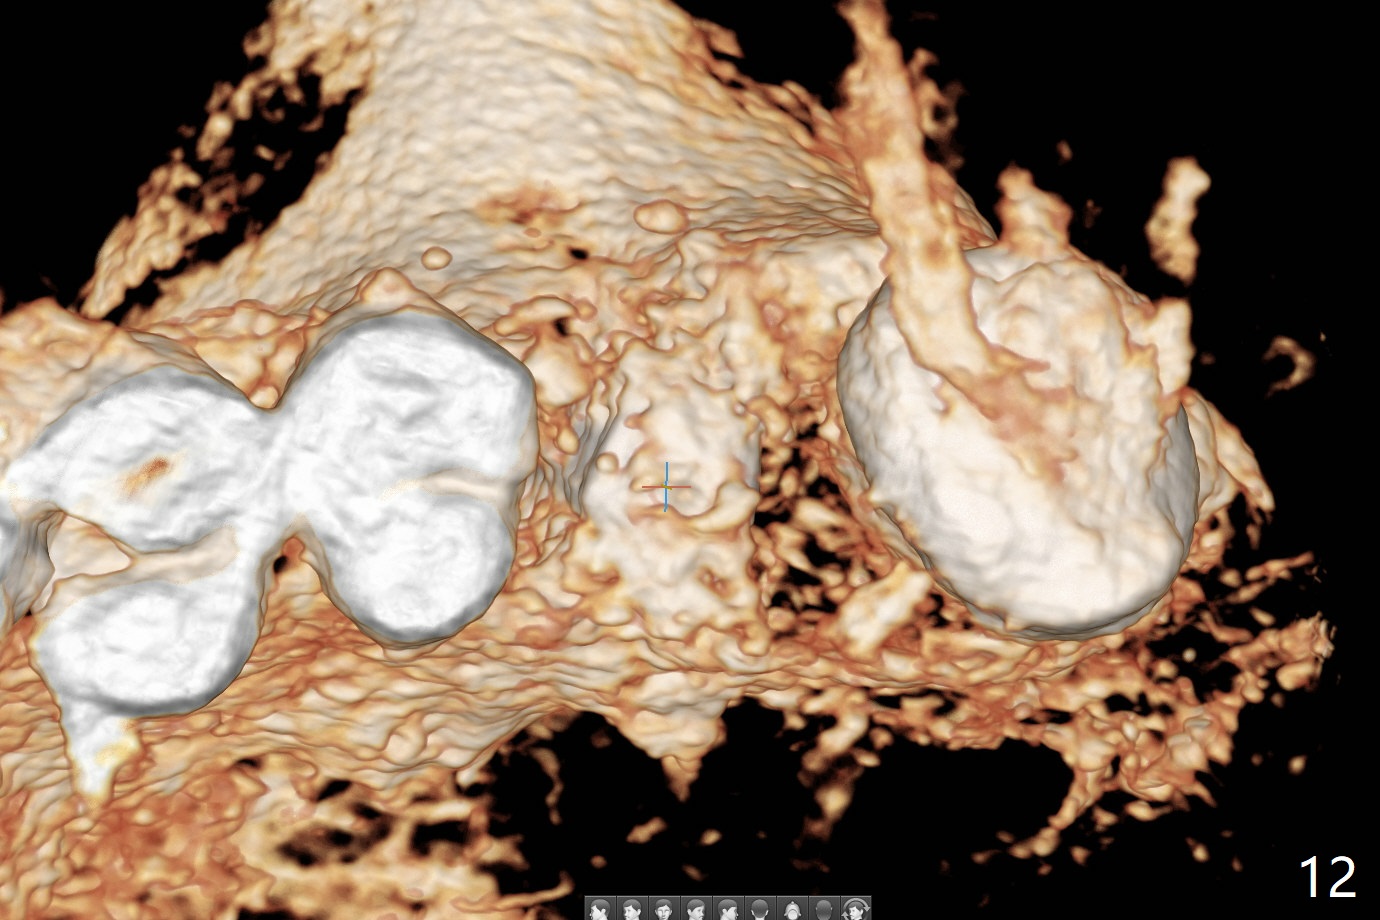

A 57-year-old woman complains of bad smell while use of water flosser between 11 and 21 months post cementation of implant crown at #14 (Fig.1,2). Bone loss is more obvious with CBCT (Fig.3,4), in spite of apparently normal gingiva around the implant after removal of the abutment and crown (Fig.5). In fact the buccal (B) gingiva is fragile with easy access to the underlying implant plateau. Following flap elevation, the bone loss is evident (Fig.6), but the implant plateau is slightly subcrestal (Fig.7 *). The exposed implant threads are covered with the 1st round of bone graft (Fig.8). After 2nd round of allograft (Fig.10-12) and collagen membrane, the flaps are approximated (Fig.9). The wound is covered by acrylic dressing. The latter is loose, but stays in place 1 week postop (Fig.13). Due to short neighboring teeth, the acrylic dressing is able to be removed with wiggling; it appears that the wound is healing (Fig.14). The dressing returns for another 2 weeks; some of the graft has been lost (Fig.15). The dressing does not return 7 weeks postop, since the wound is healing (Fig.16).